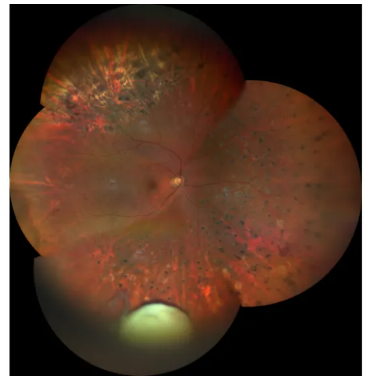

散瞳后眼底检查

怀疑右眼晶状体脱位于后极略颞下方眼底,故进行了散瞳后眼底检查,发现坐位下可见晶状体于后极部,需进一步切除残余皮质,避免内源性眼内炎、葡萄膜炎等。

4.术中同时实施右眼玻璃体腔切除术,以清除残余晶状体核及皮质,从而预防内源性眼内炎、葡萄膜炎、视网膜脱离等并发症。

在本次病例中,术前检查显示晶状体已完全混浊。前节OCT检查表明后囊存在缺损,而B超提示“右眼颞下方玻璃体腔可见环形强回声影,后极部视网膜略增厚”,散瞳后发现部分晶状体落入玻璃体腔。基于这些检查结果,我们采用了飞秒辅助的phaco+IOL+玻切术。由于患者存在后囊缺损,术中采用“IOL前囊夹持”技术,将IOL的光学部分夹持在前囊口后方,利用前囊膜来固定IOL。

3.对于后囊存在缺损的白内障患者,术前需对囊袋的完整性和眼底状况进行严格检查。除了白内障皮质吸收外,晶状体膨胀也可能导致晶状体脱位至眼底。